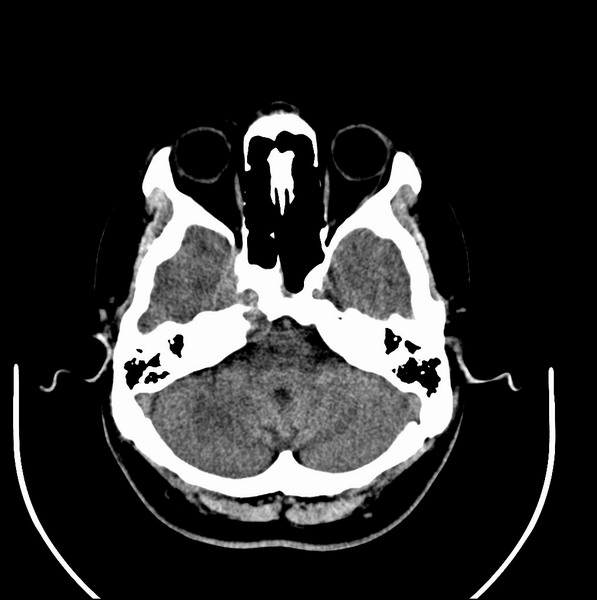

扫描示鼻咽腔不对称,中度狭窄,右侧咽隐窝消失,局部软组织肿块,鼻咽右侧壁增厚形成肿块,突入鼻咽腔,肿块平扫呈等密度,肿块向深部侵润,右侧翼内外肌受侵,右侧咽旁间隙变窄;向后生长,头长肌界线欠清,向后上生长侵犯同侧颈动脉鞘区。双侧海绵窦增宽,内见软组织影与鼻咽部肿块相连。考虑鼻咽癌。鼻咽癌主要是放射治疗,且效果较好;到当地有治疗设备较大医院治疗即可。

这个病例有点特殊,和常见的鼻咽癌不太一样,以向颅内侵犯为主,骨质破坏区小。鼻咽癌首先要考虑,有没有其他可能?本人不会看mr片,期待有人能讲解,期待病理。

鼻咽部新生物(纤维血管瘤?鼻咽癌?)侵犯右侧中颅窝底及右侧海绵窦;建议必要时活检定性。

鼻咽部新生物侵犯右侧中颅窝底及右侧海绵窦,鼻咽癌可能性大。建议增强扫描。纤维血管瘤禁忌穿刺。

典型鼻咽癌侵犯右侧海绵窦(对放疗敏感)